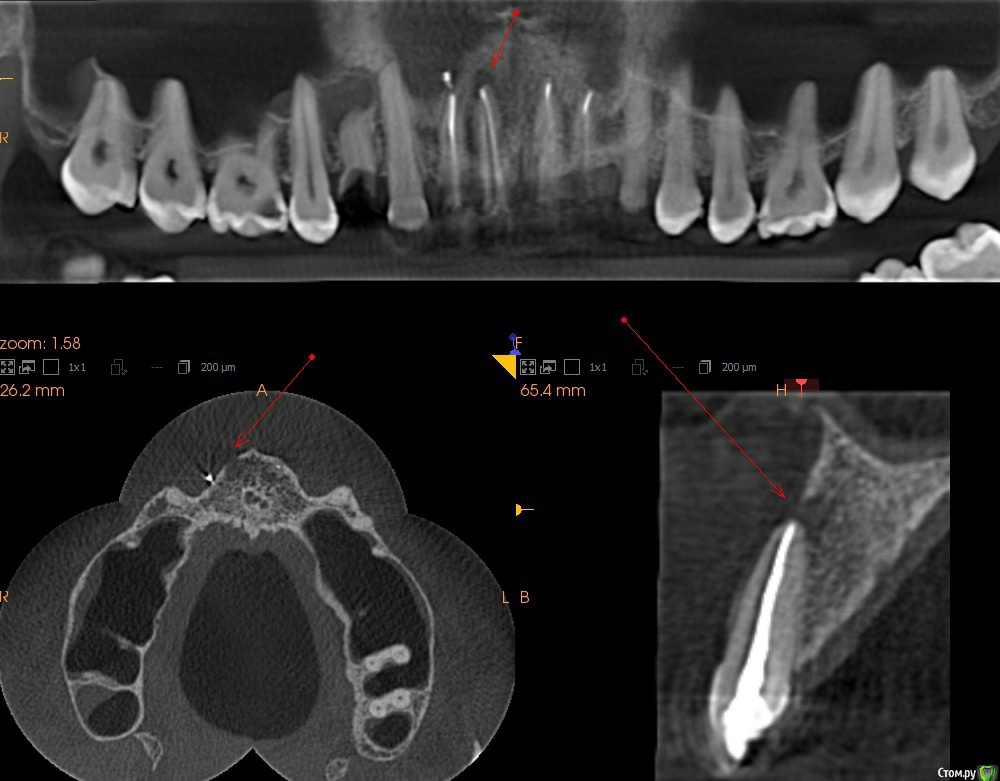

Andrian Опубликовано 26 августа, 2019 Автор Поделиться Опубликовано 26 августа, 2019 (изменено) Сделал кт. Может кто-нибудь посмотреть и что-нибудь сказать? Мне кажется или есть воспаление?https://yadi.sk/d/0xAl0w0RH3f2tg Изменено 26 августа, 2019 пользователем Andrian Ссылка на комментарий

Andrian Опубликовано 17 сентября, 2019 Автор Поделиться Опубликовано 17 сентября, 2019 Здравствуйте. Припухлость десны сохраняется на уровне 2х 3х недельной давности. Врач предлагает завершать лечение, ставить штифт и пломбировать, далее наблюдаться несколько месяцев, делать повторное кт, и если улучшений нет обращаться к члх, чтобы он через разрез в десне все там вычистил. Вынимать гуттаперчу и лечить через канал наотрез отказывается. Насколько это правильно и не навредит ли за такое время эта жидкость окружающим тканям? Может тогда лучше идти к члх прям сейчас? Ссылка на комментарий